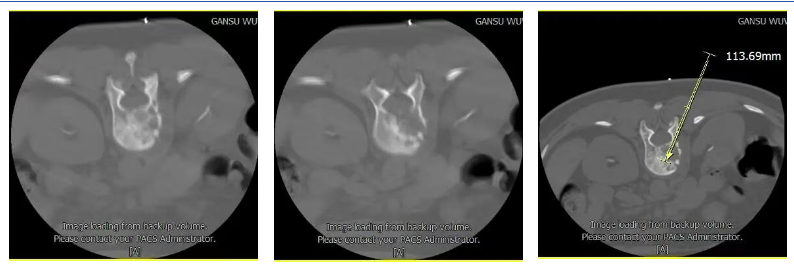

我院借助先进的大孔径CT影像设备进行引导,利用CT扫描数据,进行穿刺计划的设计,以精准的穿刺路径准确到达病变椎体,进行骨水泥注射,能够做到穿刺过程中重要组织无损伤,骨水泥注射量精准控制的目的。

比如以下病例:患者女性,既往肺部病变,经过多家医院就诊,诊断为为肺部恶性肿瘤,进行免疫靶向治疗。PET-CT检查提示多部部位转移病灶形成。我院MRI检查提示T12L1椎体病变,考虑转移癌病变。脊柱查体:患者腰部活动受限,疼痛明显。

患者术前磁共振检查影像学表现:

患者术前的磁共振检查结果提示:L1椎体病变,结合病史考虑为转移癌。影像学评估提示L1椎体高信号表现,椎体高度未发生塌陷表现,椎管内容物无受压表现。患者临床腰椎功能活动受限,疼痛明显,相关生命体征平稳。

结合患者影像学检查和临床表现,认为患者存在L1病变椎体成形术的适应症,完善相关检查及术前准备后,予以患者CT引导下的椎体成形术。

a:CT扫描确定病变部位,定位后设计穿刺路径,测量进针深度和角度;